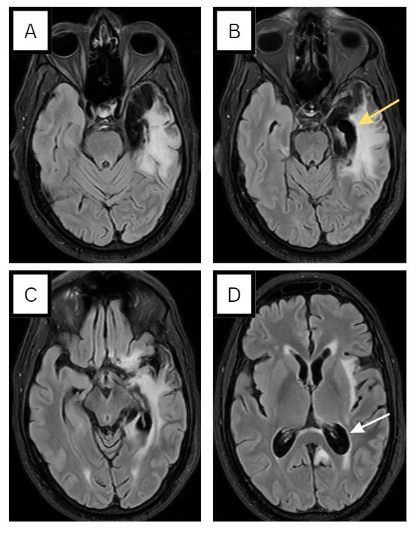

MRI was repeated and showed left temporal cortical/subcortical areas exhibiting encephalomalacia/gliosis (see Figure 4), with no evidence of restricted diffusion, thereby making stroke unlikely. An 18-channel awake EEG showed continuous focal epileptiform discharges over the left central parietal region, as quasi periodic discharges, over a background activity of moderate slowing (see Figure 5). This determination led to the diagnosis of postencephalitic non-convulsive status epilepticus. In light of this, the dosage of levetiracetam was escalated from 500mg BID to 1500mg BID. An EEG the following day showed resolution of status epilepticus but continued to display epileptiform discharges over the left fronto-central regions (Figure 6A). Consequently, lacosamide 200mg BID was introduced and EEG recorded 1 day later indicated the resolution of epileptiform discharges (Figure 6B). Upon discharge, the patient exhibited significant improvement in his clinical condition. Although he still experienced some baseline word-finding difficulty, his speech was notably more comprehensible. Additionally, he demonstrated no difficulty in responding to commands. It is important to note that the patient was an expatriate worker, and unfortunately there was loss to follow-up post-discharge.

In a retrospective review of patients with prior HSVE, postencephalitic epilepsy was noted in 45.5 % of the patients3. The predominant seizure patterns in postencephalitic epilepsy were unilateral temporal, bilateral temporal and multifocal or generalized with the majority of patients reporting an aura5. The high incidence of late unprovoked seizures following HSE may be due to the necrotizing nature of HSV-1 infection and involvement of the highly epileptogenic mesial temporal and basi-frontal cortices2. For example our patient’s repeat MRI scan showed the devastating impacts HSV can have on the brain including the profound atrophy of the left mesial temporal regions.

Concerning seizure control in postencephalitic epilepsy, there are no randomized controlled trials on the efficacy of antiepileptic drugs and their combinations, and current recommendations are based on expert opinion5. At the time of early seizure recurrence, many of the patients will be on phenytoin, valproate or levetiracetam if seizures presented during the acute phase of HSVE. Our patient was on levetiracetam when he presented with non-convulsive status epilepticus months following the acute phase of HSVE. Despite increasing levetiracetam dose our patient’s EEG showed some epileptiform discharges (Figure 6A) and therefore lacosamide was added with good effect on patient’s clinical status and resolution of epileptiform discharges (Figure 6B). Regrettably, epilepsy following HSVE typically proves resistant to treatment with antiepileptic drugs5, therefore follow up is very important in such cases. A pre-surgical evaluation with special consideration of neuropsychological performance can be done to define the subgroup of patients with a chance for favorable outcome.